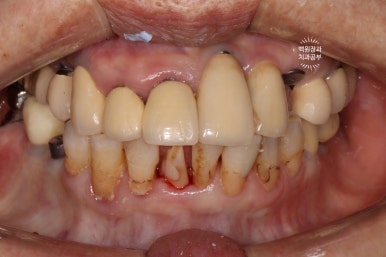

처음 오셨을 때 정면 사진입니다.

잘 보시면, 아까 보였던 치과용 파노라마 사진대로 뿌리만 남은 두 개의 치아를 찾아보실 수 있으실거에요. ㅎㅎ

제가 서두에서 어금니에 스트라우만 임플란트가 많다고 말씀드렸는데, (나머지도 branemark 제품으로 보이며, 명품으로 주름잡던 스웨덴 임플란트 입니다.) 이 미친 퍼포먼스의 스위스 임플란트는 20년이 지난 지금도 짱짱한 성능을 자랑하고 있답니다.

오스템임플란트도 신뢰하며 좋아하는 제품이긴 하지만, 60년 이상의 역사를 자랑하는 임플란트 원조격인 스위스의 스트라우만 임플란트는 진짜.. 미쳐버릴 것 같은 신뢰도를 자랑하고 있었습니다.

사실 구강위생관리가 그렇게 완벽하신편이 아니신데도.. 이런 임상결과를 보이고 있는 것이 늘 경이롭습니다.